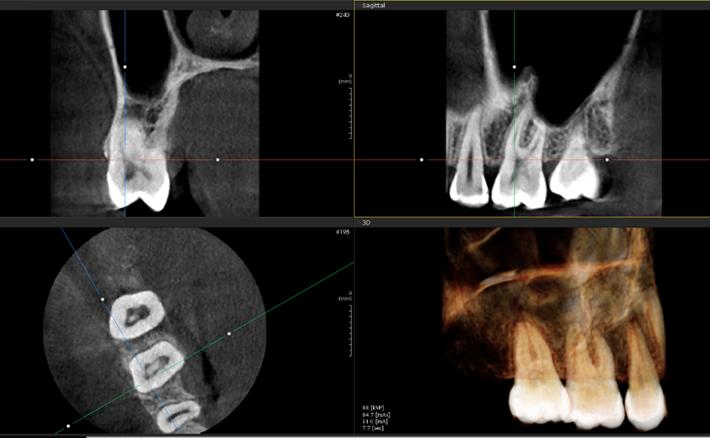

Est. Nicole Emily Rojas Espinoza1 Dr. Juan Pablo Torrico Vilte2

1 Estudiante, Carrera de Medicina, Universidad Privada del Valle. Sede Cochabamba, Bolivia. ren2015280@est.univalle.edu 2Docente, Carrera de Medicina, Universidad Privada del Valle. Sede Cochabamba, Bolivia. jtorricovilte@gmail.com

Recibido:5/1/2023 Revisado:10/5/2023 Aceptado:10/5/2023

Cita: Est. Nicole Emily Rojas Espinoza, Dr. Juan Pablo Torrico Vilte; Cirugía más inmunoterapia local en el tratamiento del tumor de Buschke-Löwenstein. A propósito de un caso. Revista De Investigación E Información En Salud UNIVALLE 2022; 18(44): p.49-53 https://doi.org/10.52428/20756208.v18i44.448

Correspondencia: Est. Nicole Emily Rojas Espinoza, Cochabamba, Bolivia, +591 70797928 ren2015280@ est.univalle.edu

Nota: Los autores declaran no tener conflicto de intereses con respecto a esta publicación y se responsabilizan de contenido vertido.